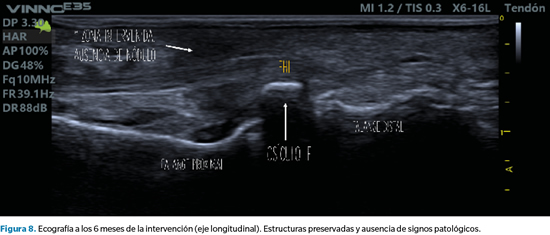

Pasados seis meses de la intervención, se volvió a citar a la paciente en consulta para revisar el caso, confirmando su total satisfacción con el resultado y la ausencia completa de síntomas. Asimismo, se tomaron nuevas imágenes del dedo y se repitió la ecografía para valorar la correcta evolución del caso, sin recurrencia de lesión plantar alguna y con una cicatriz casi imperceptible en la zona de la incisión (Figura 6, 7 y 8).